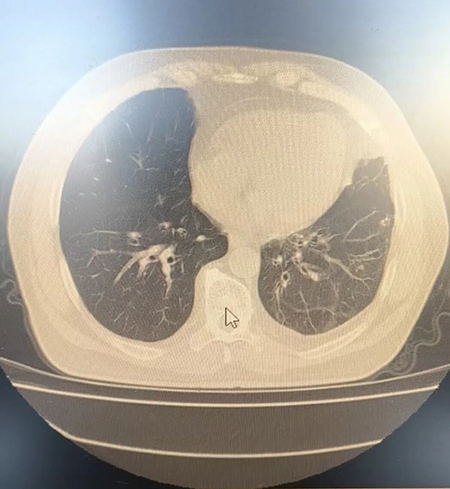

肺部CT检查显示的支气管扩张症